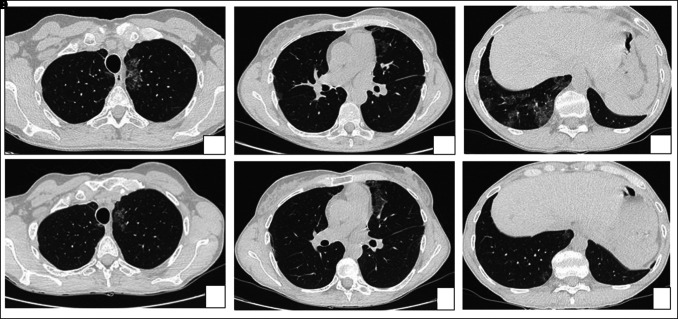

Background: Pulmonary alveolar proteinosis (PAP) has an unpredictable clinical course. Although usually benign, an association with pulmonary fibrosis is described in literature, with troubling therapeutic and prognostic implications.

Clinical case: We report the case of a patient affected by autoimmune PAP who developed pleuro-parenchymal fibroelastosis (PPFE) after 6 years of disease and underwent bilateral lung transplantation due to end stage respiratory failure.